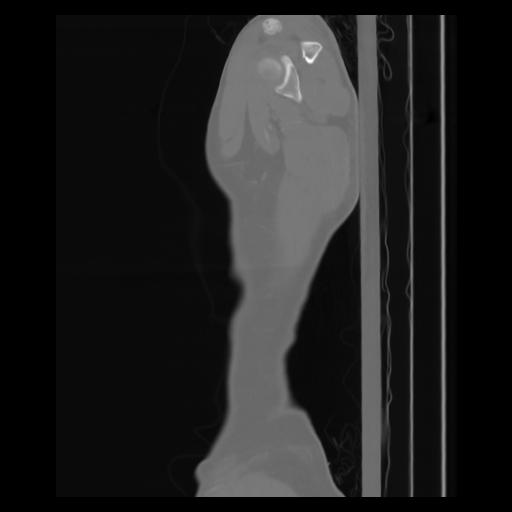

30 CUERPO,CE,Sagittal,3.000,CUERPO,Sagittal,